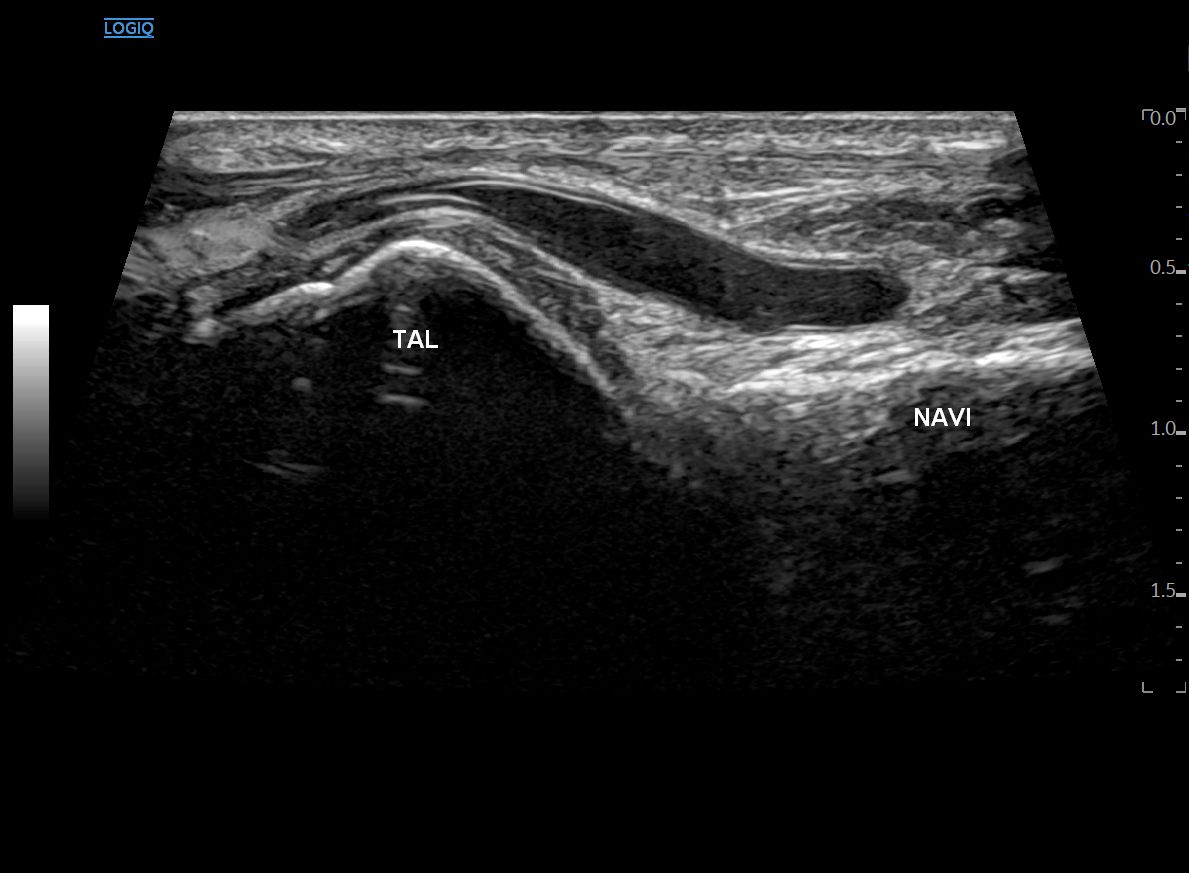

프로브로 원래 방향으로 돌려서

내측으로 이동하면

거골(TAL)의 head와 주상골(NAVI)이 보입니다.

제가 스캔한 것처럼

이분인대가 안 보이는 단비골근건부터

이분인대가 사라지는 거골까지 봐야 합니다.

그래야 놓치지 않고

전체 인대를 꼼꼼하게 검사한 겁니다.